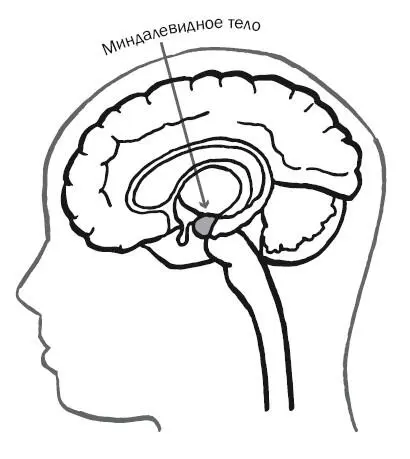

Один поток идет в гипоталамус, который помогает формировать воспоминания и обеспечивает доступ к ним. Другой поток разделяется на две части, одна из которых попадает непосредственно в миндалевидное тело, а другая заворачивает во фронтальные доли, но в итоге тоже попадает в миндалевидное тело. (Вскоре я более подробно расскажу о нем.)

К этому времени мозг получает достаточно полное впечатление о тигре, и наступает пора уведомить тело. Для этого миндалевидное тело посылает сигнал в гипоталамус (39), который является одним из самых занятых работников в нашем организме: он полностью или частично отвечает за всевозможные биологические процессы, в том числе метаболизм и гомеостаз, аппетит и либидо. (Биологи говорят о четырех категориях: питание, бегство, борьба и совокупление.) И наконец, нейроны гипоталамуса возбуждают шишковидную железу, которая, в свою очередь, вырабатывает гормоны, заставляющие нас спасаться бегством, дрожать, мочиться или иным образом проявлять эмоции на телесном уровне.

Забавным образом статья Пейпеца о лимбической системе, написанная для того, чтобы выставить организаторов гранта в глупом виде, обеспечила именно то, к чему они стремились: научное представление о работе человеческих эмоций. Но несмотря на свою гениальность, Пейпец упустил из виду один важнейший аспект лимбической системы: в его статье 1937 года ничего не говорилось о миндалевидном теле .

Получившие названия за свою форму (от греческого слова «миндаль») два отростка миндалевидного тела расположены глубоко в височных долях. Они включают состояние рефлекторного испуга, обрабатывают запахи (единственную форму чувственного восприятия, которая минует таламус) и помогают определить, на какие вещи вокруг нас стоит обращать внимание. Некоторые неврологи, обыгрывающие понятие двух потоков «что» и «где» в исследованиях зрения, относят миндалевидное тело и другие соседние структуры к потоку «ну и что из этого?». «Я это вижу , – говорит ваш мозг, – но следует ли мне беспокоиться об этом ?» Миндалевидное тело отвечает на этот запрос.

Если нам следует беспокоиться, миндалевидное тело делает следующий шаг и помогает выбрать соответствующую реакцию, особенно если эта реакция связана со страхом. Фактически миндалевидное тело часто называют «точкой страха» в нашем мозге. Это упрощение – миндалевидное тело обрабатывает множество эмоций, включая радостные, – но в нем содержится доля истины. Иметь отдельную структуру, которая определяет пугающие вещи, в целом хорошо, так как она удерживает нас подальше от хищных зверей, темных мест, страшных клоунов и так далее. Но как и любая другая часть мозга, миндалевидное тело может функционировать с нарушениями, заставляя людей постоянно бояться. Они видят несуществующие угрозы и могут сойти с ума.

С другой стороны, как показывает обследование женщины с инициалами С. М., повреждение миндалевидного тела может привести к противоположной проблеме: отсутствию страха . В детстве С. М. нормально реагировала на пугающие вещи. Однажды ночью она пошла со своим братом на кладбище и завизжала, когда он выпрыгнул на нее из-за дерева. В другой раз, когда доберман-пинчер зажал ее в углу, она почувствовала, как сердце замерло, а желудок провалился куда-то вниз. Это типичная реакция испуга. Но примерно в возрасте десяти лет она пострадала от болезни Урбаха – Вите, редкого недуга, который омертвляет и убивает клетки миндалевидного тела. Через несколько лет она имела две «черных дыры» там, где обычно находились отростки миндалины. С тех пор она вообще не испытывала страха.